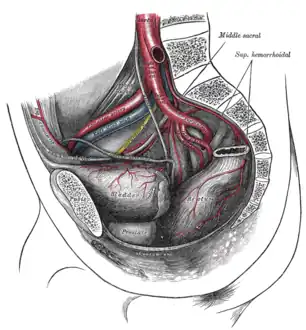

Arteries

Joints of the pelvis. Anterior view. The arteries of the pelvis.

The arteries of the pelvis. Dissection of side wall of pelvis showing sacral and pudendal plexuses.

Sacral plexus of the right side. Male pelvic cavity

Male pelvic cavity Female pelvic cavity